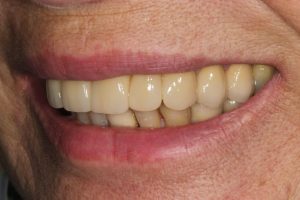

Upper Front Tooth Implant

Both upper front teeth were in a bad way, the upper left one had to be removed as was beyond repair, this was replaced with an implant and a temporary crown on the same day; the upper right front tooth was repaired with a crown. Photos show the result with the definitive crowns after 3 months of treatment.